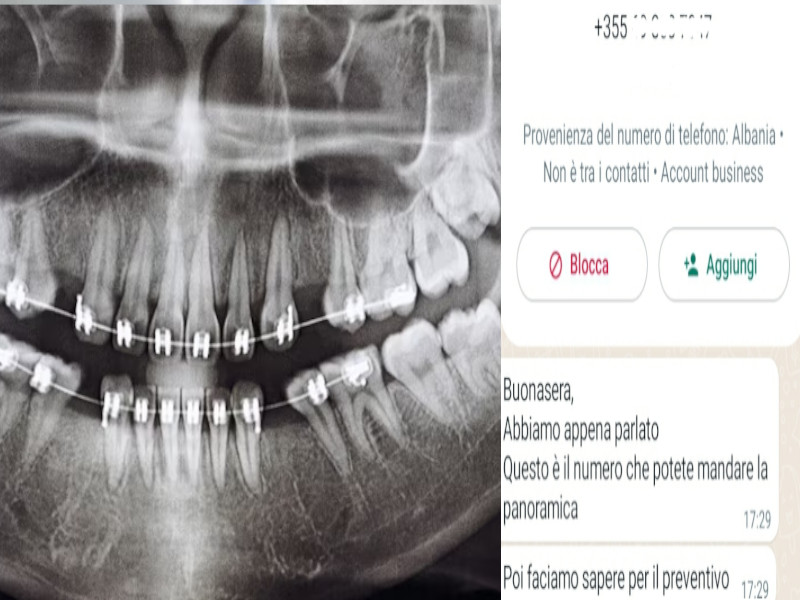

La telefonata arriva da un numero di cellulare con prefisso italiano, la voce è di chi finge di essere italiana ma nasconde le vere origini: “Sono Elisa, sto chiamando per il turismo dentale in Albania, se avete problemi con i denti”. L’accento è dell’est Europa, male andando delle repubbliche ex sovietiche, ma la tiritera è detta in italiano impeccabile: “È un servizio tutto compreso. Volo andata e ritorno a Tirana, albergo e accompagnatore dall’hotel alla clinica”. Più la cura di una o più carie, una devitalizzazione o qualche altro danno ai denti: “È il chirurgo che fa il preventivo”. Su cosa? “Dovete mandare la panoramica dentale su Whatsapp”. Evviva la tecnologia, verrebbe da pensare. Peccato che, poi, il numero dal quale parte il messaggino con la richiesta sia un altro, prefisso +355, quello dell’Albania. In pratica, ci si deve fidare di una donna, che non spiega come faccia ad avere l’utenza privata di un sardo, ( “ah, capisco…”, questa la risposta a metà tra l’irrazionalità e un Renato Pozzetto in gran spolvero) e che sostiene cure a prezzi convenienti ma solo dopo che ha la radiografia della bocca del possibile cliente di turno. Ovviamente, il passo successivo da fare è semplice: non rispondere al messaggio via Whatsapp, perchè sennò si rischia di entrare in un vortice di messaggi che hanno un’unica finalità: convincere la persona a prenotare quanto prima l’intervento.